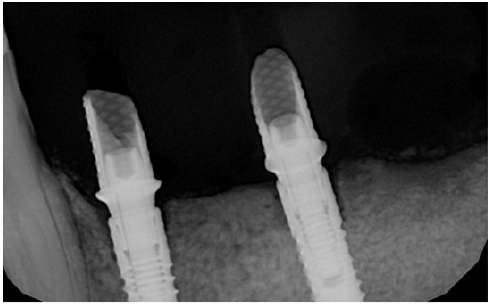

Figure 21: Standard diameter 3.4 mm implants placed six months after augmentation.

Figure 22: Three year follow up shows perfect stability of the regenerated bone aftyer loading.